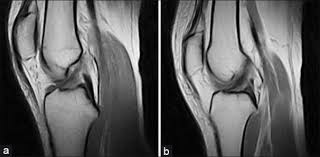

Knee Ligament Injury Causes And Healing A Ligament Tear Mri Plus

Knee Ligament Injury Causes And Healing A Ligament Tear Mri Plus from mriplus.co.uk

As a result, the joint may show abnormal looseness. A grade 2 sprain stretches the ligament to the point where it becomes loose. Some surgeons describe a grade four injury, also called a medial column injury, to the mcl. (minor sprain) high signal is seen medial (superficial) to the ligament, which looks normal grade 2: Partial tear of the ligament, leaving a small feeling of instability. This usually causes some instability in your knee joint. Some mild knee tears may not limit your ability to walk or cause serious discomfort. Grade 2 symptoms are considered moderate with significant pain and tenderness on the inside of the knee with some swelling.